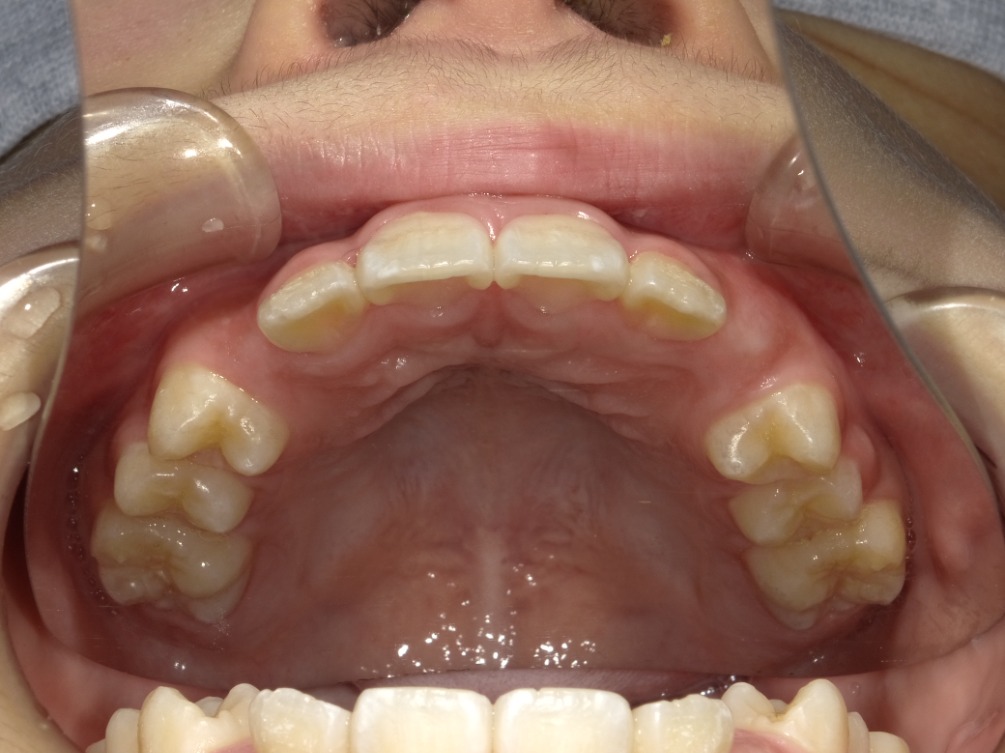

• BEFORE

症例集 インビザライン 上顎

矢印

AFTER

上顎